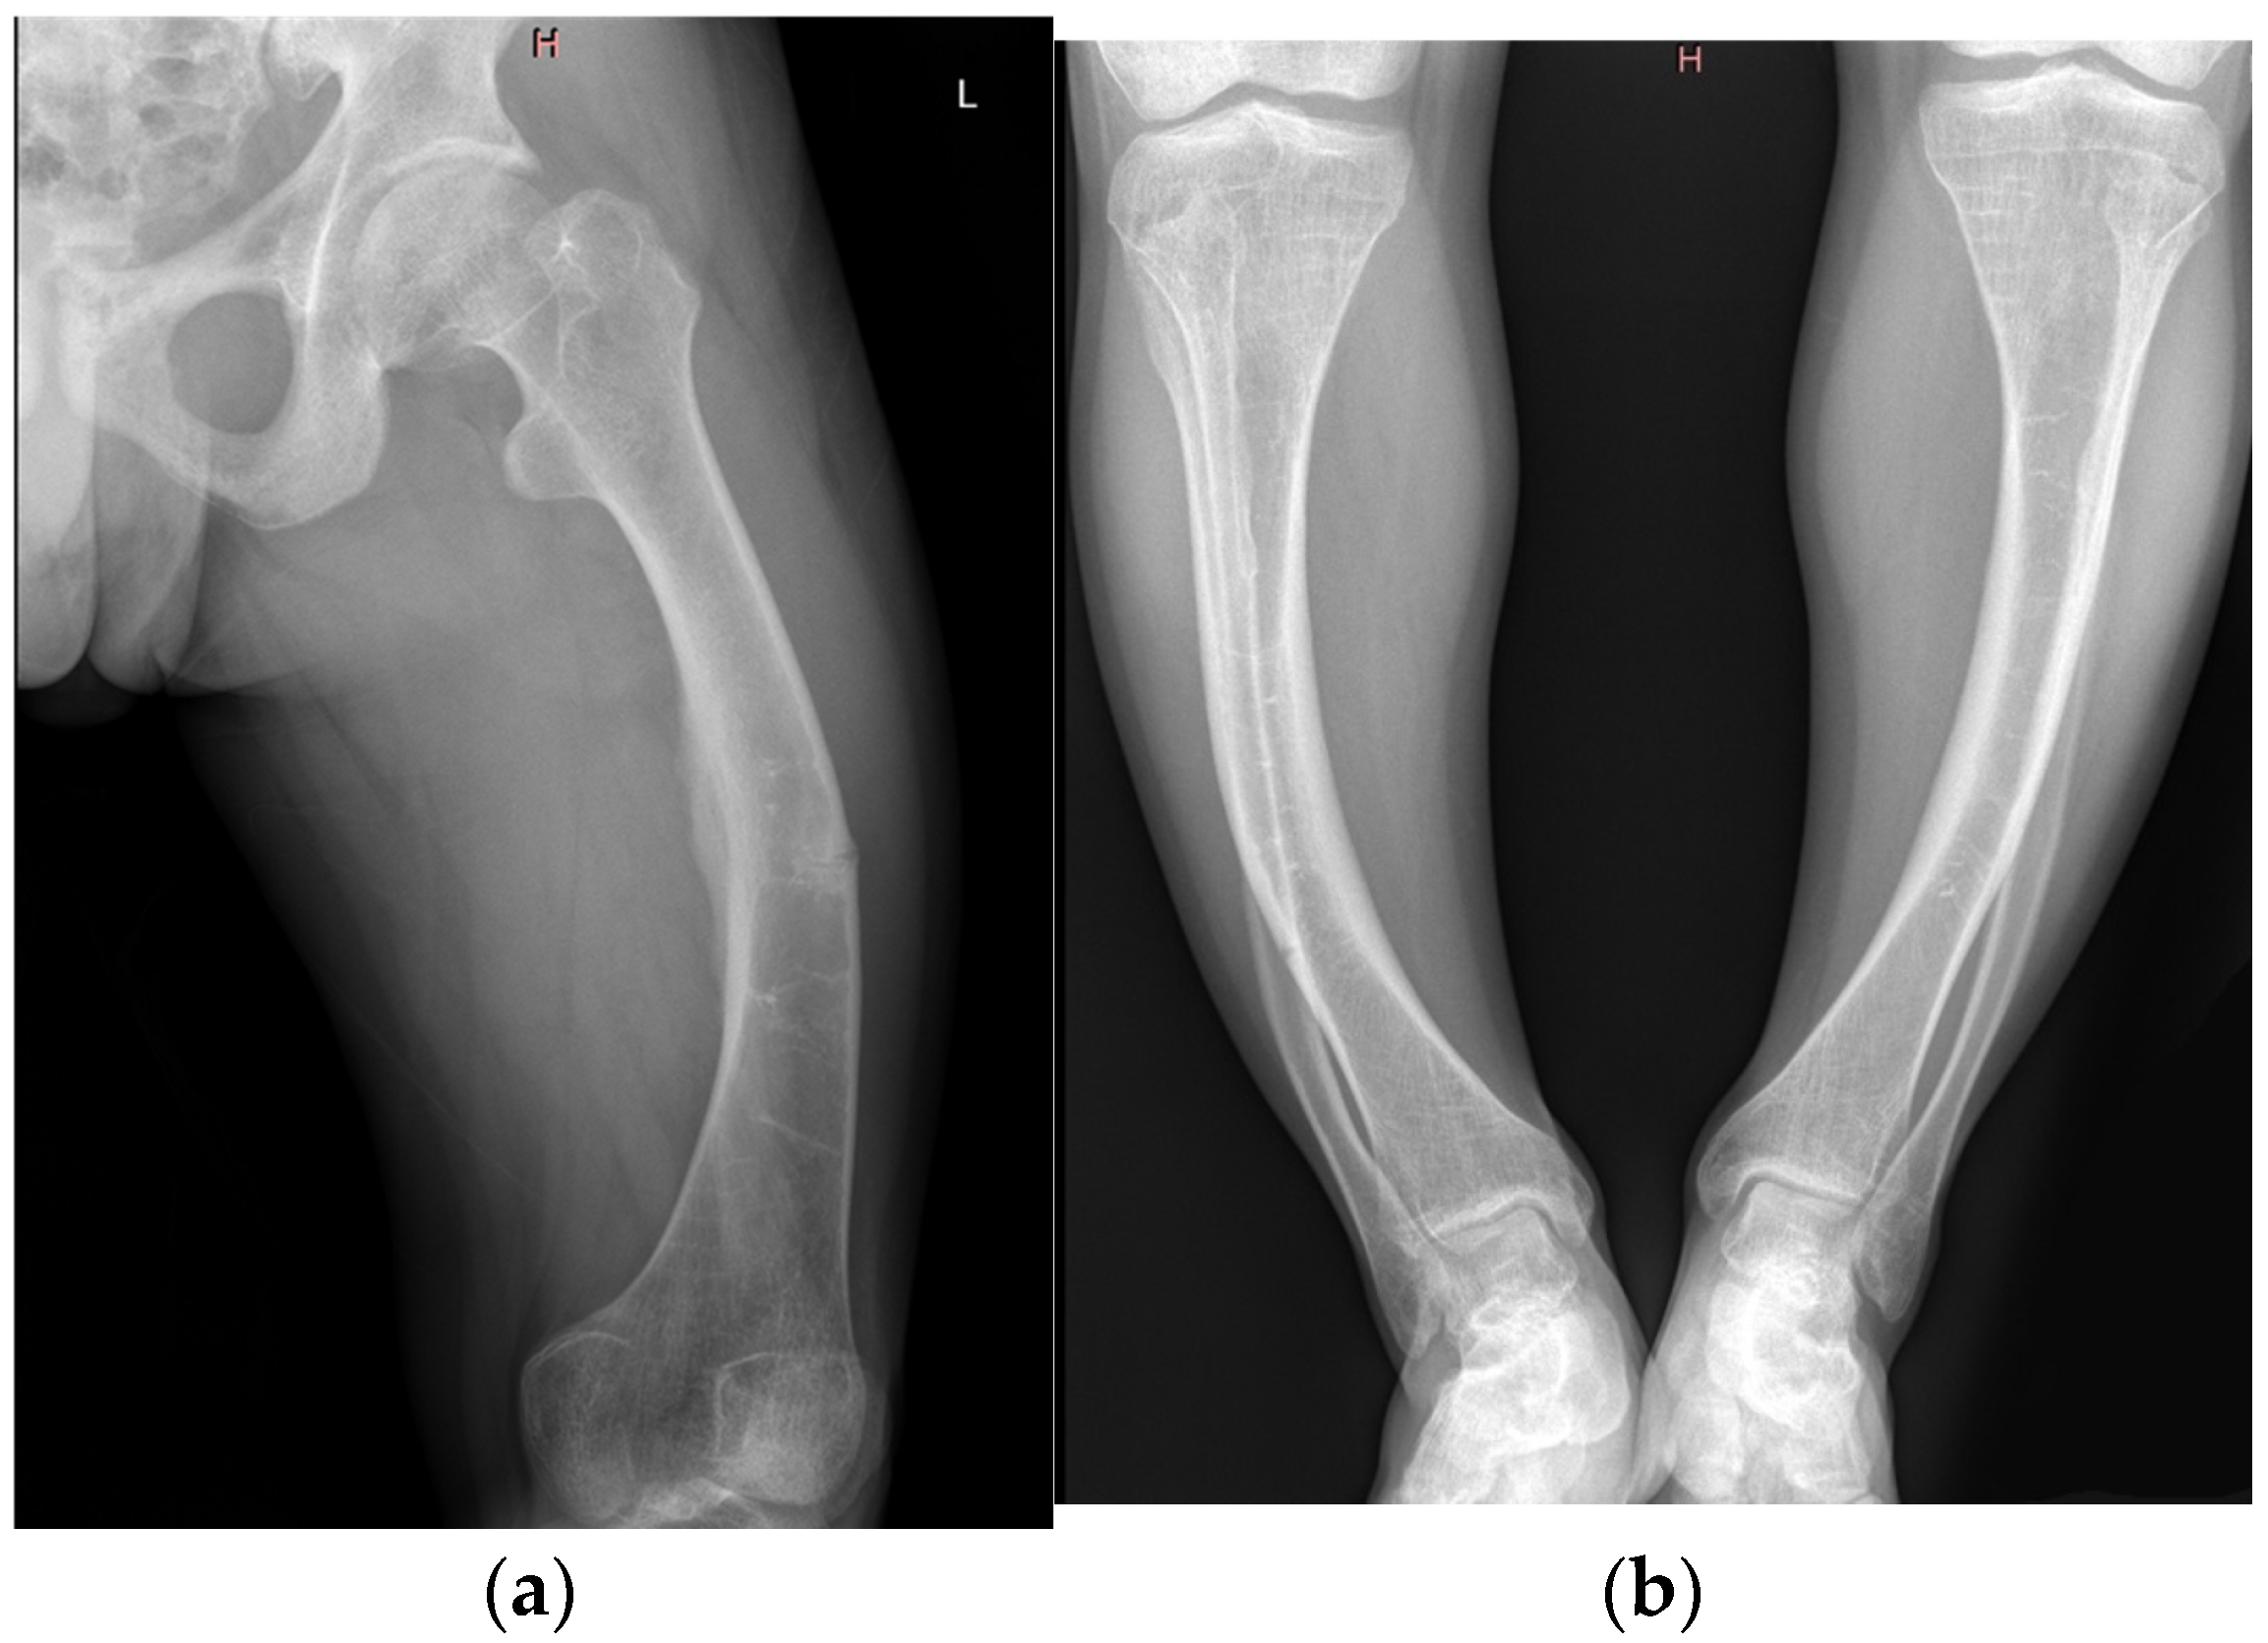

| Imaging findings | Radiography | Bowing of femurs and tibiae, pseudofracture in mid-femur |

| Imaging findings | Radiography | Bone demineralization, bilateral coxarthrosis and gonarthrosis, genu varum |